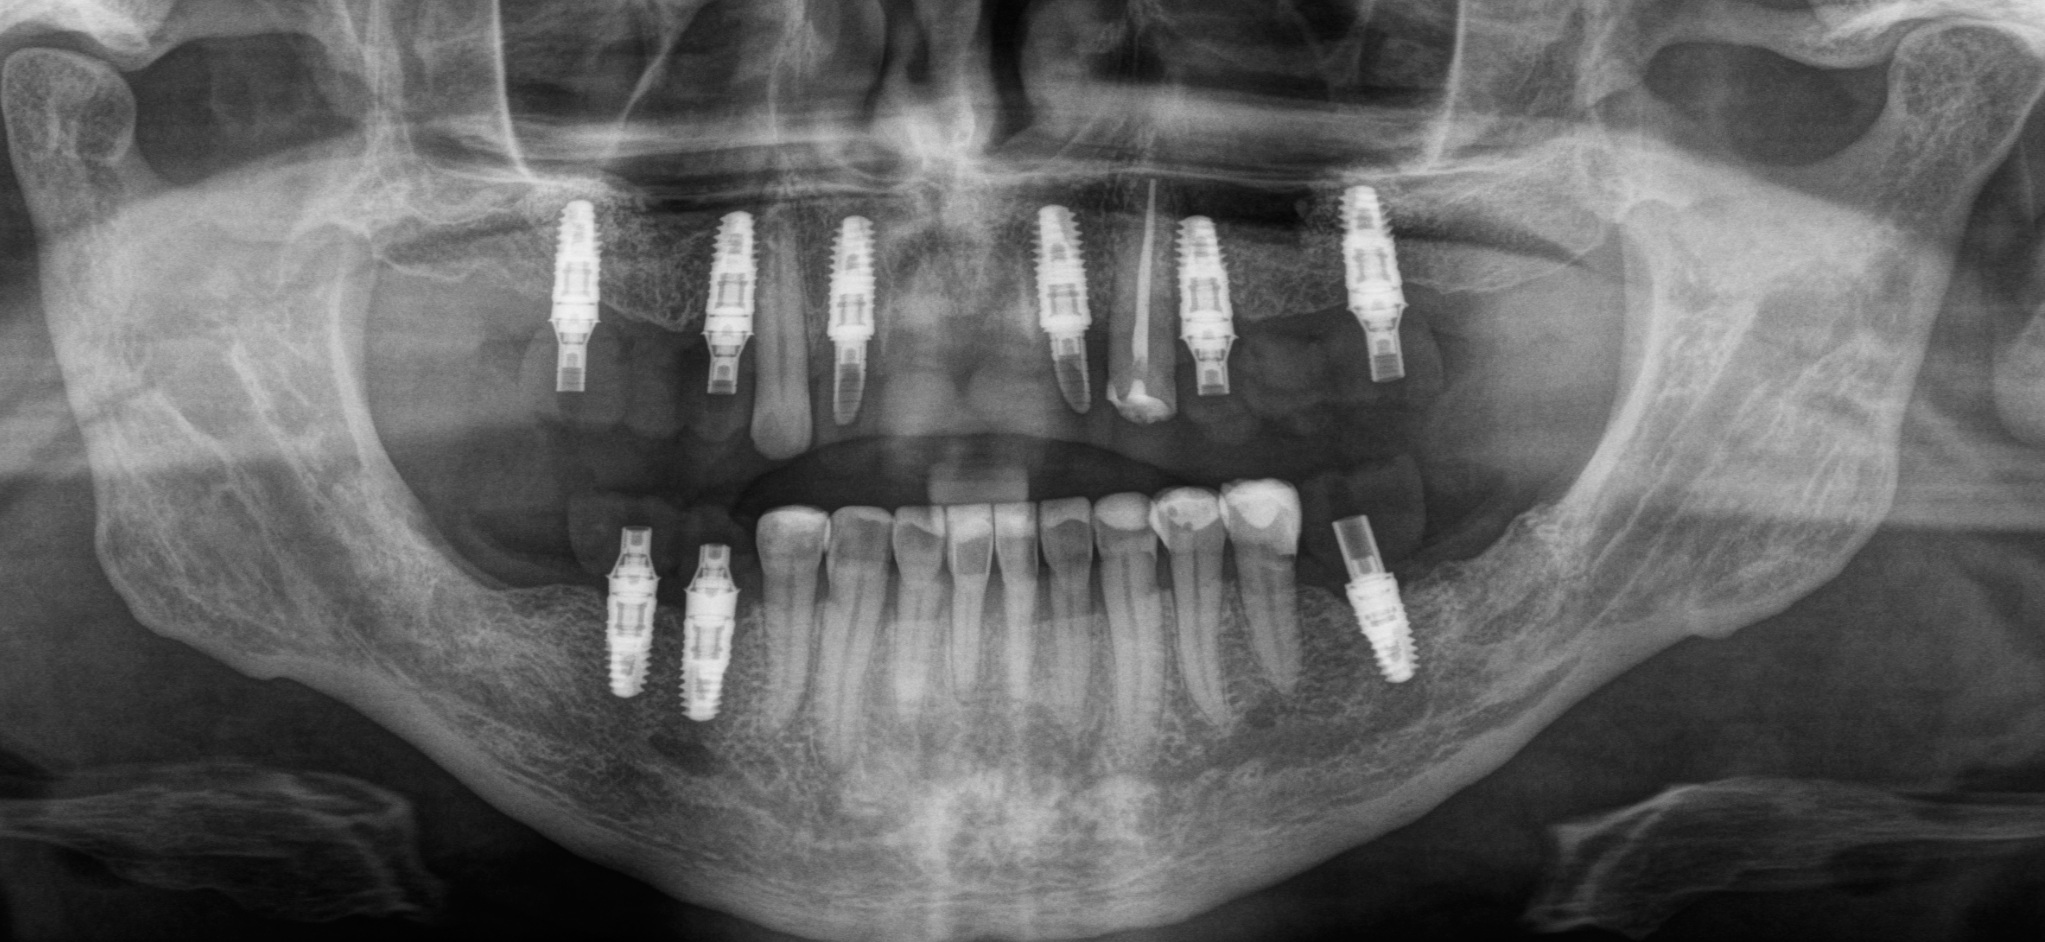

Дабы не перегружать вас обилием одинаковых картинок, я оставлю один рентгеновский снимок, но отмечу, что установка имплантатов на верхней и нижней челюсти проводилась с разницей в 10 дней.

На верхней челюсти было дополнительно удалено два боковых резца с одномоментной установкой имплантатов, так же они были установлены в области четверок и шестых зубов. Дополнительно было проведено наращивание костной ткани - двусторонний синус - лифтинг. О том, что это такое, можно почитать ТУТ и ТУТ.

Контрольный рентгеновский снимок:

Вот так было:

А как стало на промежуточном этапе:

Согласитесь, выглядит очень даже неплохо, если опустить цвет.